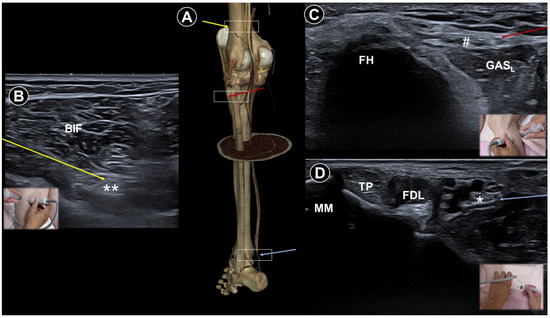

- Hung, C.-Y.; Hsiao, M.-Y.; Özçakar, L.; Chang, K.-V.; Wu, C.-H.; Wang, T.-G.; Chen, W.-S. Sonographic tracking of the lower limb peripheral nerves: A pictorial essay and video demonstration. Am. J. Phys. Med. Rehabil. 2016, 95, 698–708. [Google Scholar] [CrossRef]

| Painful radiculopathy | Pain, numbness, clumsiness and even weakness in the distribution of the affected nerve root | Mechanical compression and inflammatory irritation of the nerve root, often due to disc herniation or spondylosis | Cervical: supine, head turned to contralateral side Lumbar: prone | Cervical: linear, in-plane

| Improvement of pain by ESI (meta-analysis), SNRB/caudal block (RCT) |